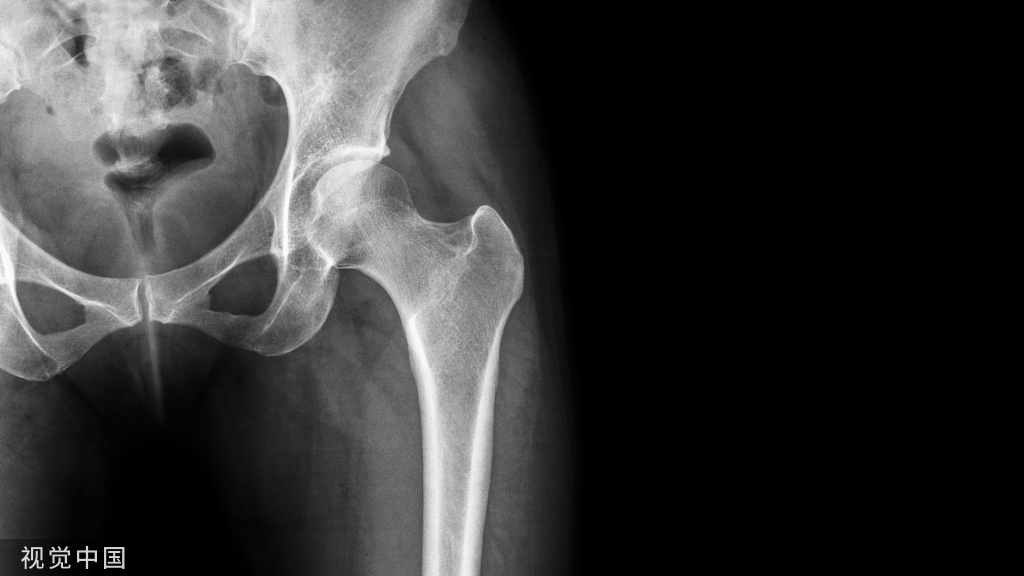

将克氏针紧贴于骨表面插入,可以为后续的钻孔、置入螺钉提供导向作用,提高成功率,常用于骨盆、股骨颈、股骨髁等位置。